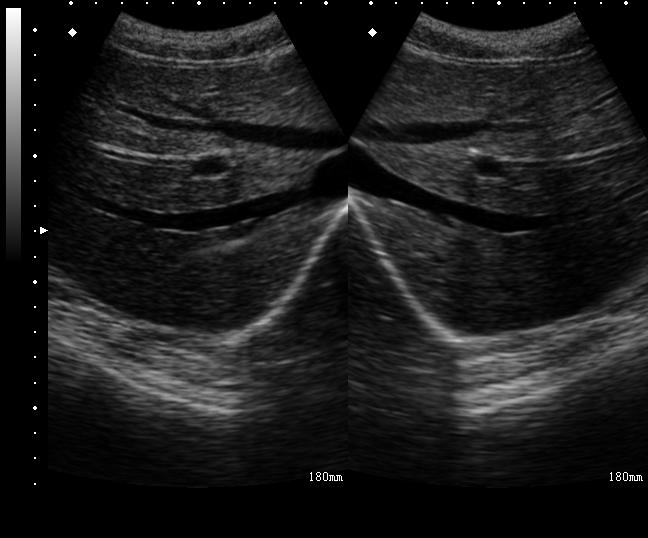

第6~12肋间神经斜向内下,行于腹内斜肌与腹横肌之间,并进入腹直肌鞘,在腹白线附近浅出,称为前皮支,支配胸腹部近正中线区域。可用于腹壁局限性手术麻醉和作为腹部大手术多模式镇痛的一个部分。选用6~13MHz的高频超声探头和短轴平在面技术。在腋中线的肋弓下缘区域放置探头,分辨出腹外斜肌、腹内肌和腹横肌用平面内技术将针尖置于腹内斜肌和腹横肌筋膜之间,回抽无血,注射15~20ml局部麻醉药(图27-1,图27-2)。